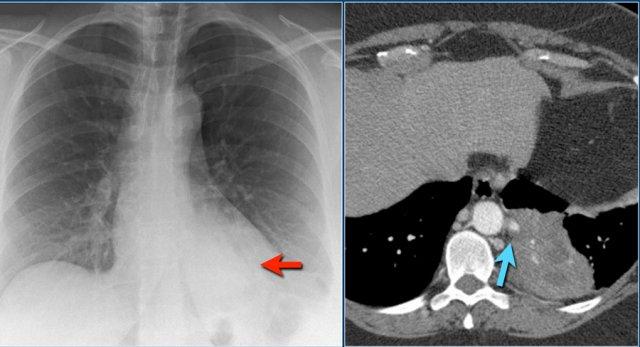

Phổi biệt lập (Pulmonary sequestration)

Đây là nguyên nhân không phổ biến gây đông đặc thùy.

Đây là một bất thường bẩm sinh.

Một phần phổi không hoạt động thiếu sự thông thương với cây phế quản và nhận nguồn cung cấp máu động mạch từ tuần hoàn hệ thống.

Bệnh nhân biểu hiện với nhiễm trùng tái phát khi vi khuẩn di chuyển qua các lỗ Kohn.

Lưu ý động mạch nuôi dưỡng phân nhánh từ động mạch chủ (mũi tên xanh).